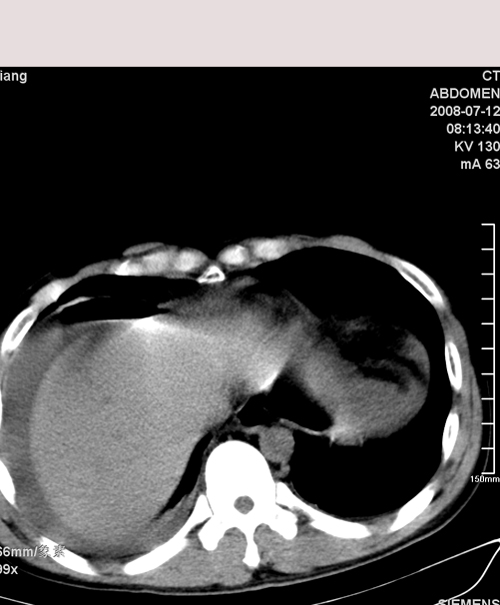

以下是引用muzi888在2008-7-15 10:45:00的发言:[br]大量腹腔积液,气腹,肾皮质弧形高密度影,诊断;1 空腔脏器穿孔 2 右肾包膜下血肿

以下是引用随光逐影在2008-7-15 11:18:00的发言:[br]考虑为:1)腹部空腔脏器穿孔。2)右肾破裂并肾包膜下血肿,肾盂积血。3)腹水(血)。